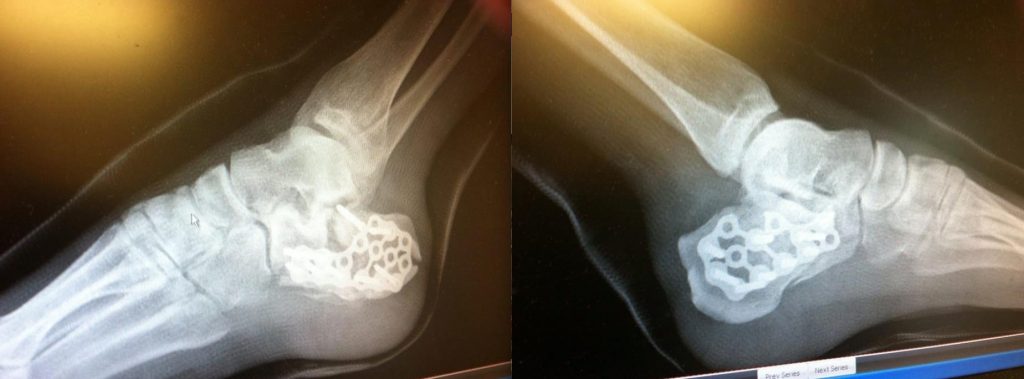

I came from South Georgia with dreams of climbing and flying as a kid. The moth to the flame mentality. I started climbing when I got insurance and learned the ropes in the mountains of N. GA and N. Carolina. I got certified to skydive in Tallahassee, FL around age 28. Fast forward ten plus years and one divorce later. I managed to make a bad decision and do a BASE jump I was not prepared for and shattered my heels and broke a few other things. I laid in a hospital bed for 5 plus months.